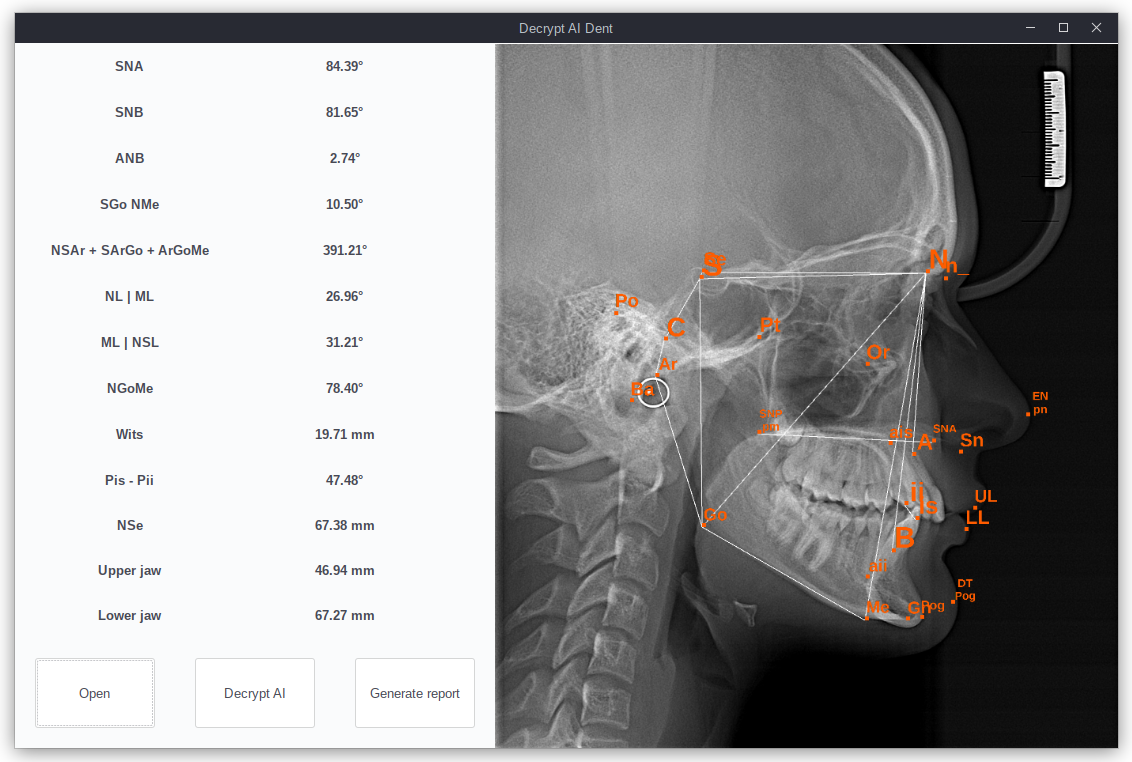

The interaction of the end-user with the software package should not be complicated and should not create obstacles before using neural network algorithms. The concept of an intuitive interface is the leading one in the design of a software package. At the first stage of development, for testing the software package on a pilot group of doctors to identify problems and assess the quality of the software package, we created a simple interface that provides image loading, automatic decoding using convolutional neural networks, and generating a report.

At the moment, the test interface with the ability to manually correct automatic decoding by moving the position of the marked reference points shown in Fig. 4. It should be noted that the presented interface is not the final version and serves to collect feedback and suggestions from the end-users of the test group, namely, a group of practicing orthodontists who agreed to test the developed software package.